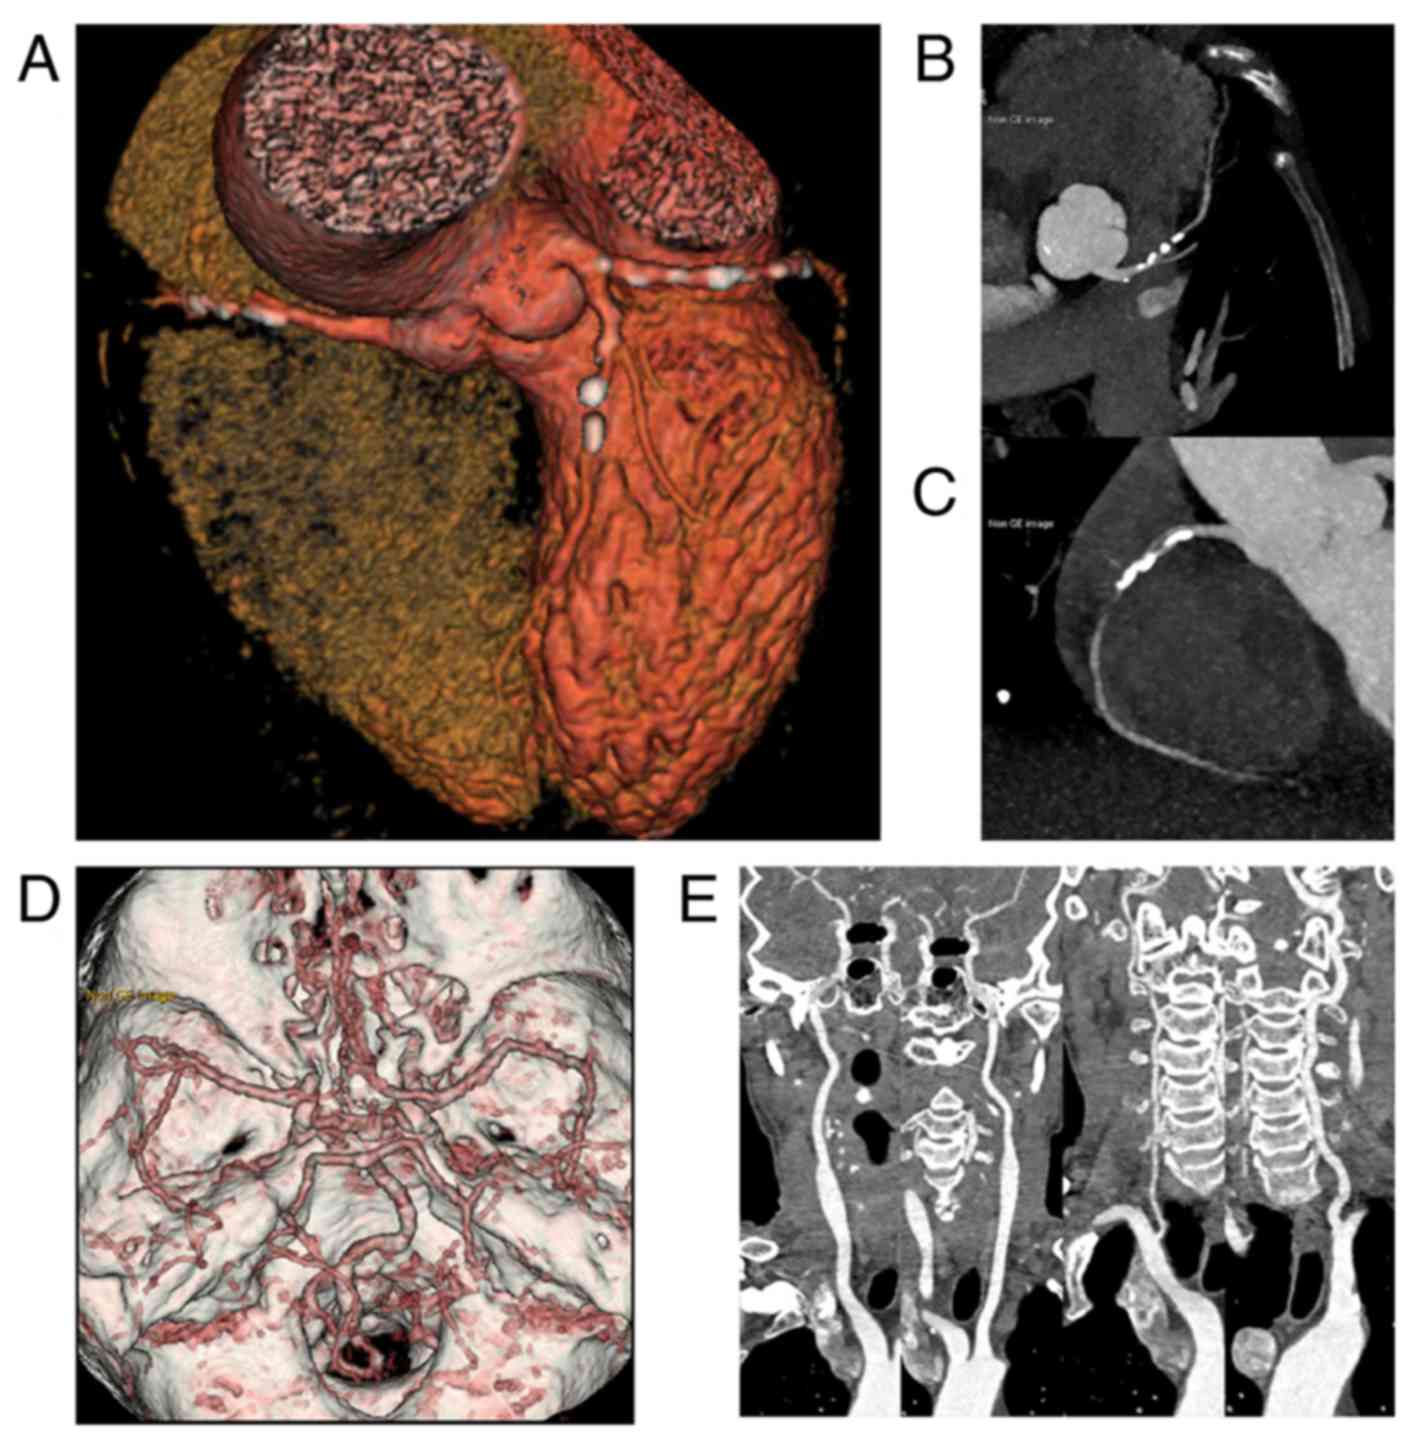

Figure 2 from A Large Isolated Congenital Left Circumflex Artery-to …

Isolated hypoplastic circumflex coronary artery: a rare cause of …

Computed tomography. Huge left circumflex artery to right atrium …

Ultra‑low dose one‑step CT angiography for coronary, carotid and …